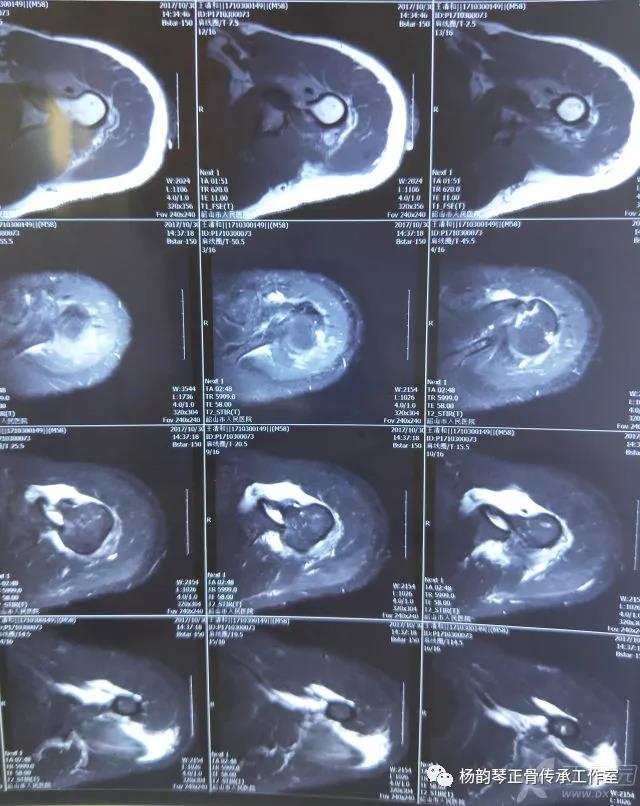

简要病史:骑摩托车跌倒致左肩部肿痛,活动受限,就诊于当地医院,拍片及磁共振检查后诊断为肩袖损伤及肩关节半脱位,予以悬吊固定,因症状缓解不明显就诊于我院。外院拍片情况如下:

磁共振检查也完善了,还是报了个肩关节半脱位……影像科已经把坑挖好了……